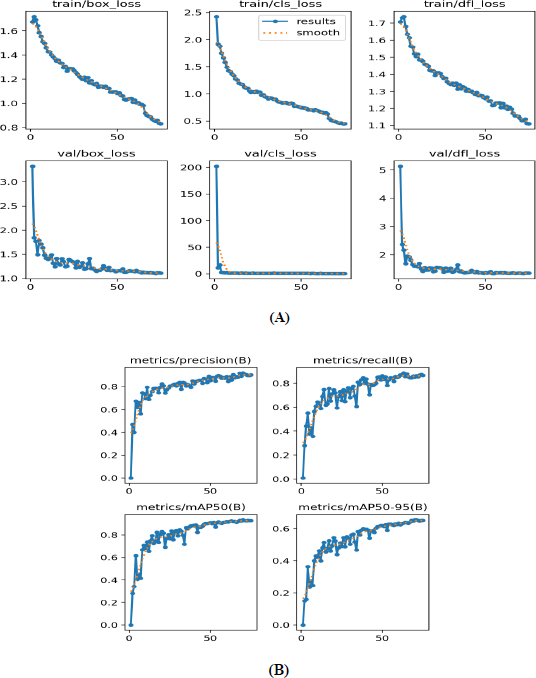

Various performance metrics of tumor detection using YOLOv12 model are shown in Fig. (5), highlighting several aspects of the model during training and validation phases over 75 epochs. During the training phase, both box loss and classification loss decreased as the number of epochs increased, indicating progressive improvement in the model’s classification capabilities. The dfl_loss is employed to increase the accuracy of bounding-box predictions, particularly for objects that are difficult to differentiate or closely resemble each other. During the model training, df_loss decreased as the number of epochs increased, demonstrating that the model accurately predicted the bounding boxes. Durning the validation, box_loss, cls_loss, and dfl_loss decreased sharply as the number of epochs increased. Finally, our YOLOv12 model achieved a precision of 90.28%, a recall of 86.66%, and an mAP50 of 92.9%. Thus, the resulting model nearly perfectly predicted tumour detection.

Performance metrics of the YOLOv12 model. (A) Loss curves; (B) Precision, recall, and mAP50 curves.